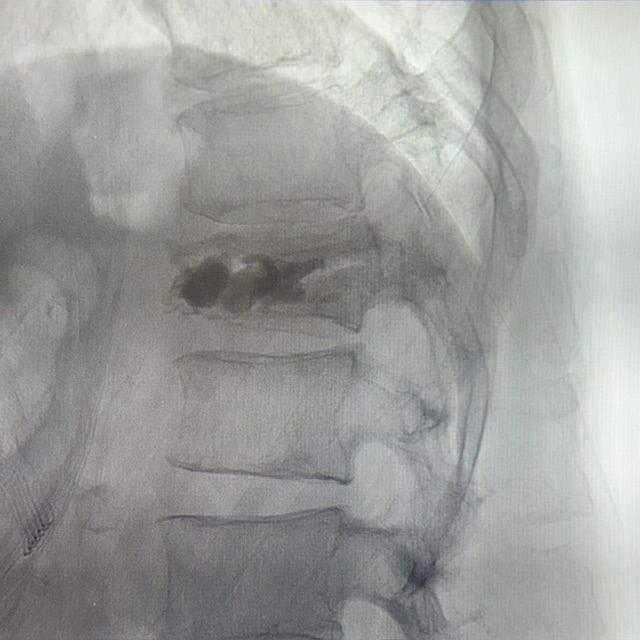

Figura 2: Imagine statică din angiografie preprocedural în plan sagital

Figura 3: Imagine statică din angiografie în plan sagital pentru poziționarea acului

Se practică kifoplastie unipediculara cu balon.